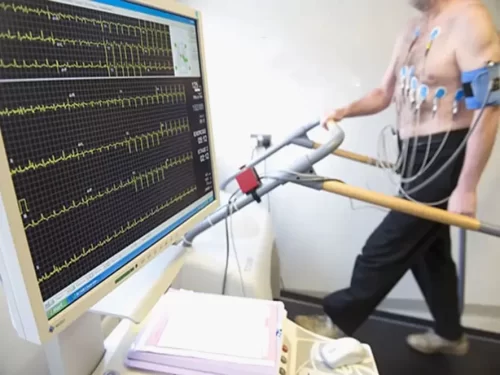

- تست ورزش

- تست استرس